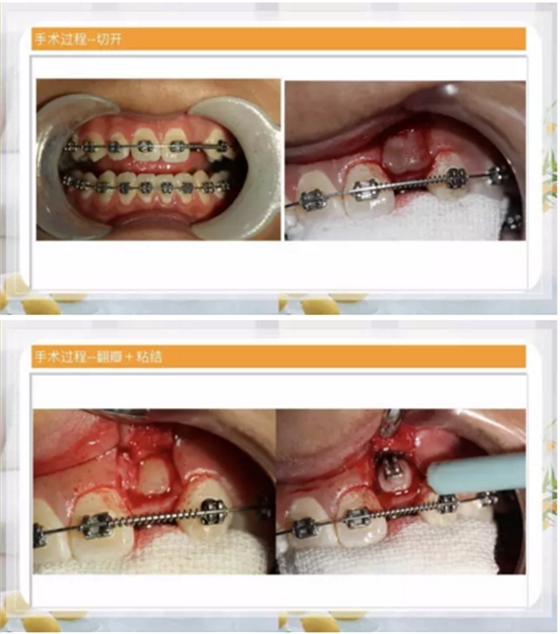

第一種方法:糾正過(guò)來(lái)!

阻生齒外科聯(lián)合正畸治療